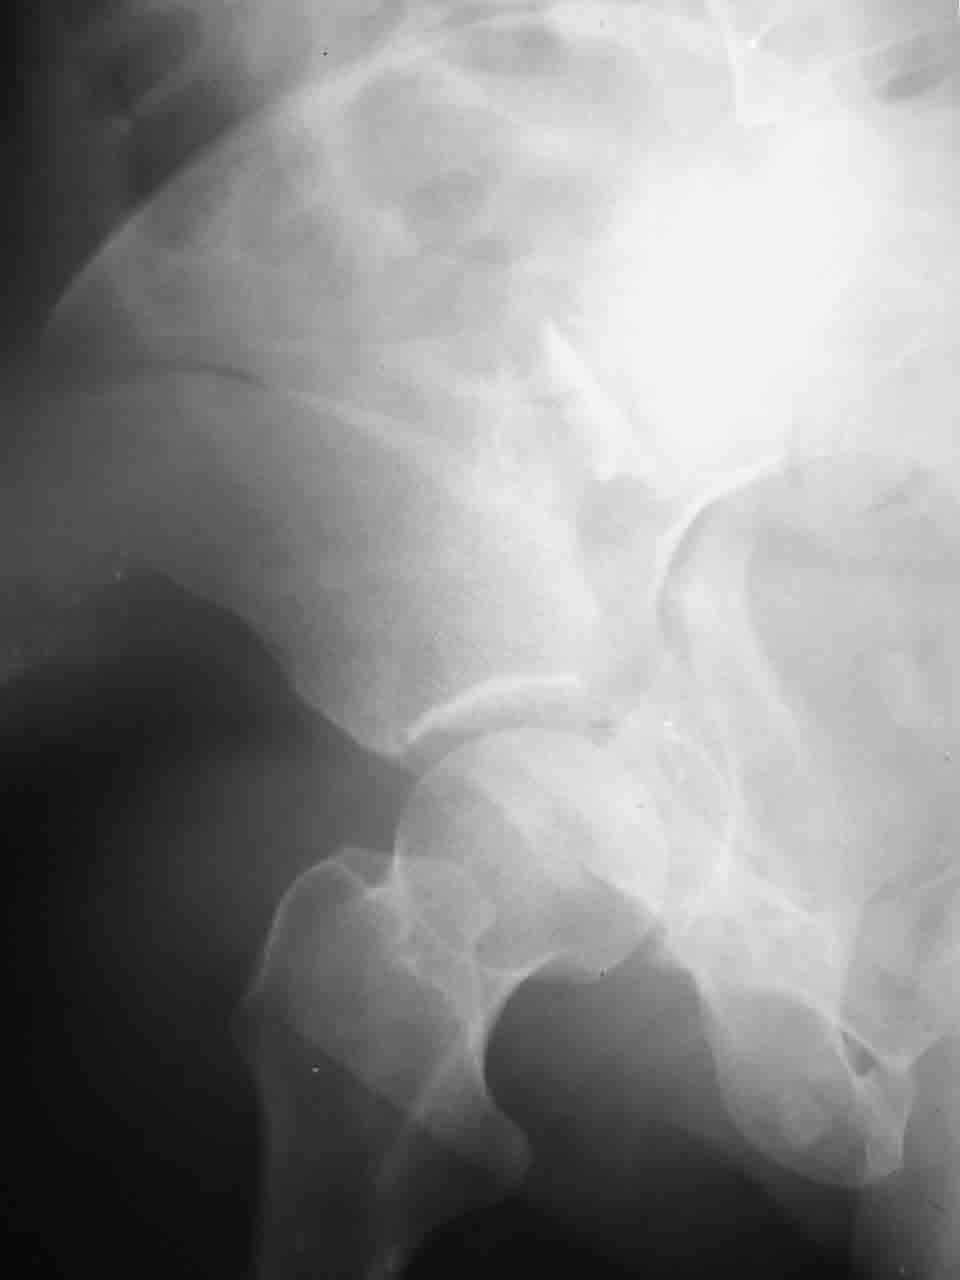

Интерес к реконструкции вертлужной впадины у меня появился довольно-таки давно, но до недавнего времени как-то не ощущалась готовность к практической реализации, а местный подход достаточно консервативен - перелом срастется,

а далее будет видно. Такую точку зрения я не разделяю, поэтому через конференции,ортофорум и свои случаи пытаюсь практически и теоретически *продвинуть* для себя тему реконструкции вертлужной впадины.

Логика подсказывает, что все-таки лучше иметь анатомически полноценную впадину, хотя ранее упоминалось состояние вторичной конгруэнтности и одно наблюдение у меня есть, когда у больного с полностью нарушенной анатомией впадины и подвывихом головки бедра кзади и кверху боли отсутствовали при относительно достаточном для стиля жизни больного объёме движений. Но это только одно наблюдение и кроме перелома впадины у этогобольного была и тяжелая ЧМТ в анамнезе. Основываясь на формулировке структуры ацетабулюм Э. Летурнеля - как перевернутой буквы Y, впадина для полноценной функции сустава должна иметь сферичность, соответствующую размеру головки бедра и если один из компонентов в дефиците, то функциональные последствия рано или поздно проявятся.

Сложностью, ассоциативностью характера перелома, я бы с радостью воспользовался мининвазивной перкутанной фиксацией винтами, но боюсь, что результат был бы ещё хуже, техникой непрямой репозиции перелома не владею, поэтому пытаясь получить анатомичную впадину приходится широко открывать, по крайней мере пока, а дальше буду пытаться уменьшать пространство...

Илеофеморальный доступ не совсем передний и сравнительно с илеоингвинальным, и Кохера-Лангенбека открывает весь наружный таз кроме самых передних отделов лонных костей, фиксацию которых я не ставил в задачу. Обширность диссекции, большая длительность операции и более высокий риск гетерооссификации - отрицательные моменты в обмен на возможность легче ориентироваться.

Вопрос доступа к вертлужной впадине при остеосинтезе задача не простая. Конечно, у Летурнеля и Тайла всё давно описано, нам остается только брать на вооружение. Но сами понимаете, что не бывает двух одинаковых ситуаций, поэтому в каждом случае вопрос решается сугубо индивидуально. Наша главная цель - восстановить анатомию с нанесением минимальной дополнительной травмы тазобедреннному суставу, думаю с этим никто не поспорит. Расширенный илиофеморальный доступ уж слишком травматичен (как сказал один коллега "таз лежит отдельно, больной отдельно").Стоит ли делать из пациента анатомический препарат для того чтобы легче ориентироваться. Да и нужно ли собирать всю "мозаику"? Мы применяли при таких операциях своеобразную операционную хитрость - сначала устраняли грубое смещение крыла под гребнем с фиксацией так называемой "плавающей" пластиной (временно фиксированной на двух винтах)- доступ или продлевали боковой, или делали небольшой дополнительный разрез над гребнем. Это позволяло устранить грубое смещение и захождение отломков тела повздошной кости, что значительно облегчало репозицию и остеосинтез впадины над сводом. Основное внимание конечно же уделяли нагружаемому задне-верхнему отделу. Сообщите ваш адрес, пришлю схемы и рентгенограммы.